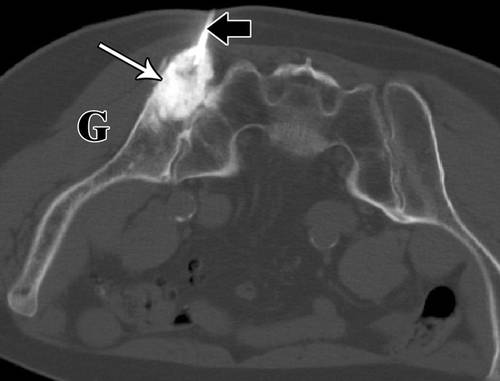

7 - 74岁男性成骨细胞性骨肉瘤穿刺。

![]()

8 - 70岁男性转移性肺癌。